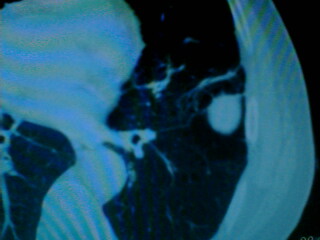

老年男性患者,右侧胸疼1月余(不是左侧),无其他症状

左肺外周类圆形病灶,其内低密度,可见液平及气影,周围肺文理见渗出样变,考虑左肺外周带肺脓肿。

左肺舌叶胸膜下卵圆形囊性肿块,内有液-气平面,邻近胸膜无增厚,没有肺窗,周围情况显示不清,考虑胸膜下肺囊肿并感染,病人年龄较大,有胸痛应警惕其他,但神经源性肿瘤暂不考虑。